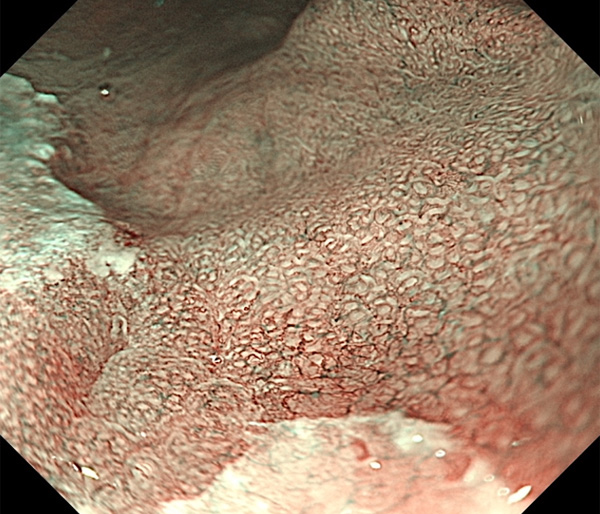

内視鏡所見と病理組織像の1対1対応が可能な症例を公募いたします。主にLSBEに発生した早期癌(HGDを含む)を対象としますが、興味深い症例であればSSBE癌でも結構です。採否は世話人へご一任ください。

特に、本邦では極めて稀なlong segment Barrett’s esophagus(LSBE)から発生した早期癌は、診断に難渋する場合も多く、欧米ではランダム生検による検出が標準的とされています。背景のBarrett食道もろとも全体を内視鏡切除+ラジオ波焼灼する欧米と異なり、ESDで内視鏡的な局所切除が基本の本邦では、存在診断+範囲診断(特に水平)を的確に行うことが不可欠です。

そのためには、一流の病理医による組織学的診断とエキスパート内視鏡医による拡大内視鏡像との一対一対応を徹底的に行うことで、『本来、見えないであろう拡大所見の先にある組織構築像が診えてくる』所まで内視鏡診断レベルを上げていく必要があります。その実現には、一対一対応を追究した症例(特にLSBE発生例)1例でも多く経験するしかありません。本研究会でBarrett食道腺癌(LSBE発生早期病変)を共に学び、拡大内視鏡像の一歩先を診るスキルを習得しましょう!一人でも多くの皆様のご参加をお待ちしています。

私は、Barrett食道癌はHGDも含め、内視鏡による存在診断、範囲診断が可能と信じて来ました。しかし最近、NBI拡大観察を併用しても側方範囲診断が不可能なLSBE症例を経験しました。診断技術を向上させるためには、多くの症例を診るしかありません。そこで、Barrett食道に造詣の深い先生方に世話人をお願いし、Barrett食道研究会を立ち上げることに致しました。全国からLSBE症例を集め、内視鏡的、組織学的診断に迫りたいと思います。皆様のご参加をお待ち致します。